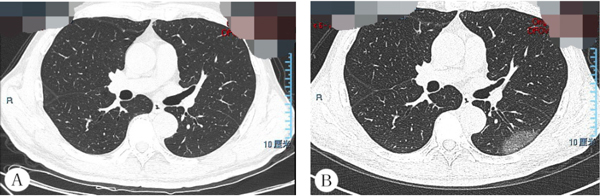

病例2,男,53岁,于1周前无明显诱因开始出现发热,最高体温达39.5°C,伴咽痛。早期胸部CT未发现异常(图2A),1周后左下肺出现局限性磨玻璃密度影(图2B)。

图2 病例2胸部CT影像表现